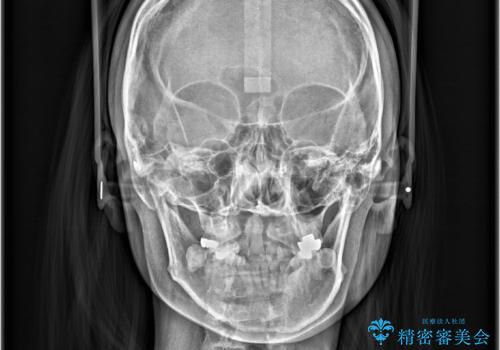

右側第二小臼歯、左側第一小臼歯、下顎両側第一大臼歯を抜歯しワイヤ-矯正を行いました。

骨格的顎の変位を認めたため、顔貌に対しピッタリ上下の歯の正中を合わせることは難しいと説明し、上下左右計4本小臼歯を抜歯しワイヤー矯正治療を行いました。